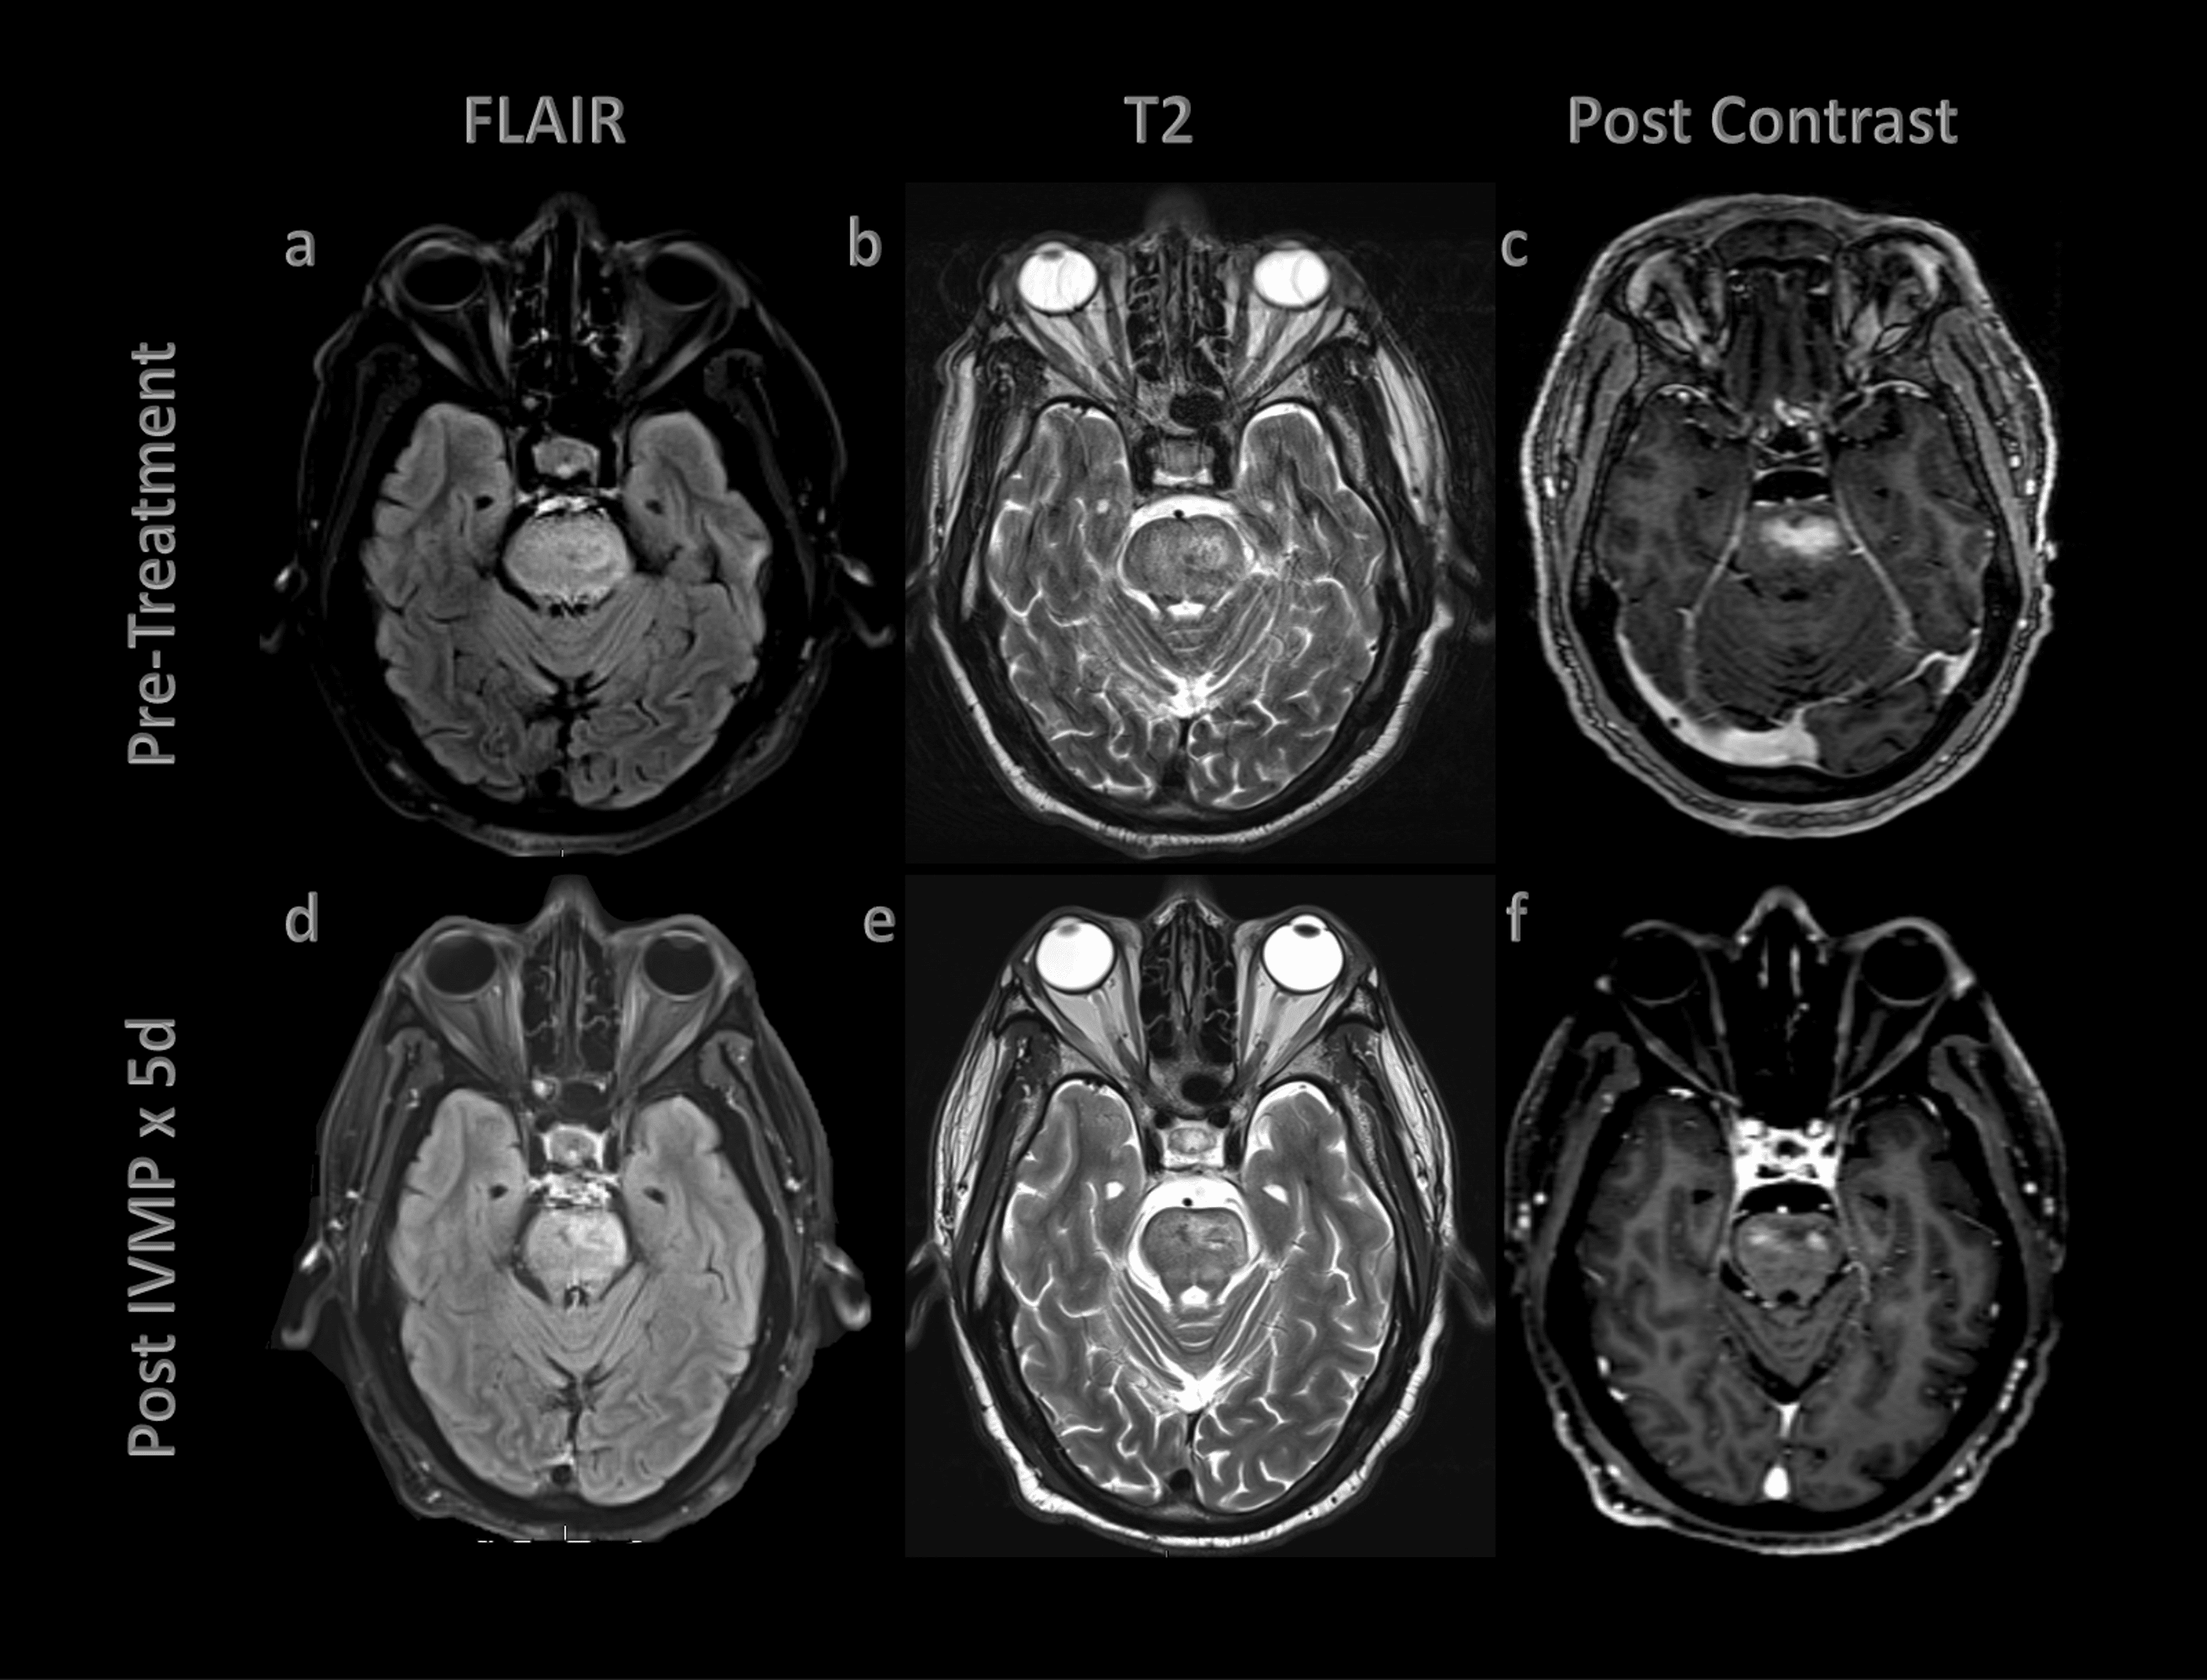

(PDF) Response to immunotherapy in CLIPPERS syndrome Is Clippers Disease Curable Symptoms are subacute, progressive, and episodic, making diagnosis difficult. chronic lymphocytic inflammation with pontine perivascular enhancement responsive to steroids. the clinical presentation of clippers is variable; the underlying pathogenesis of clippers has not been fully elucidated, and a neural autoantibody target has not been. chronic lymphocytic inflammation with pontine perivascular enhancement responsive to steroids (clippers) is. Is Clippers Disease Curable.